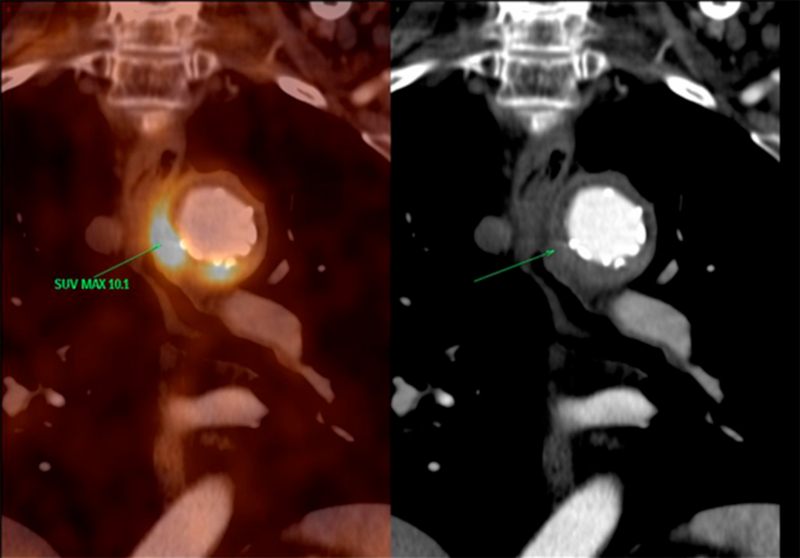

Se realizó una nueva PET/TC con F18-FDG de control evolutivo a los 2 meses (Figura 2), donde se observó persistencia de la actividad metabólica en pared medial e inferior del cayado aórtico, y extensión hacia su sector lateral, y los mismos valores de captación que en el estudio previo.